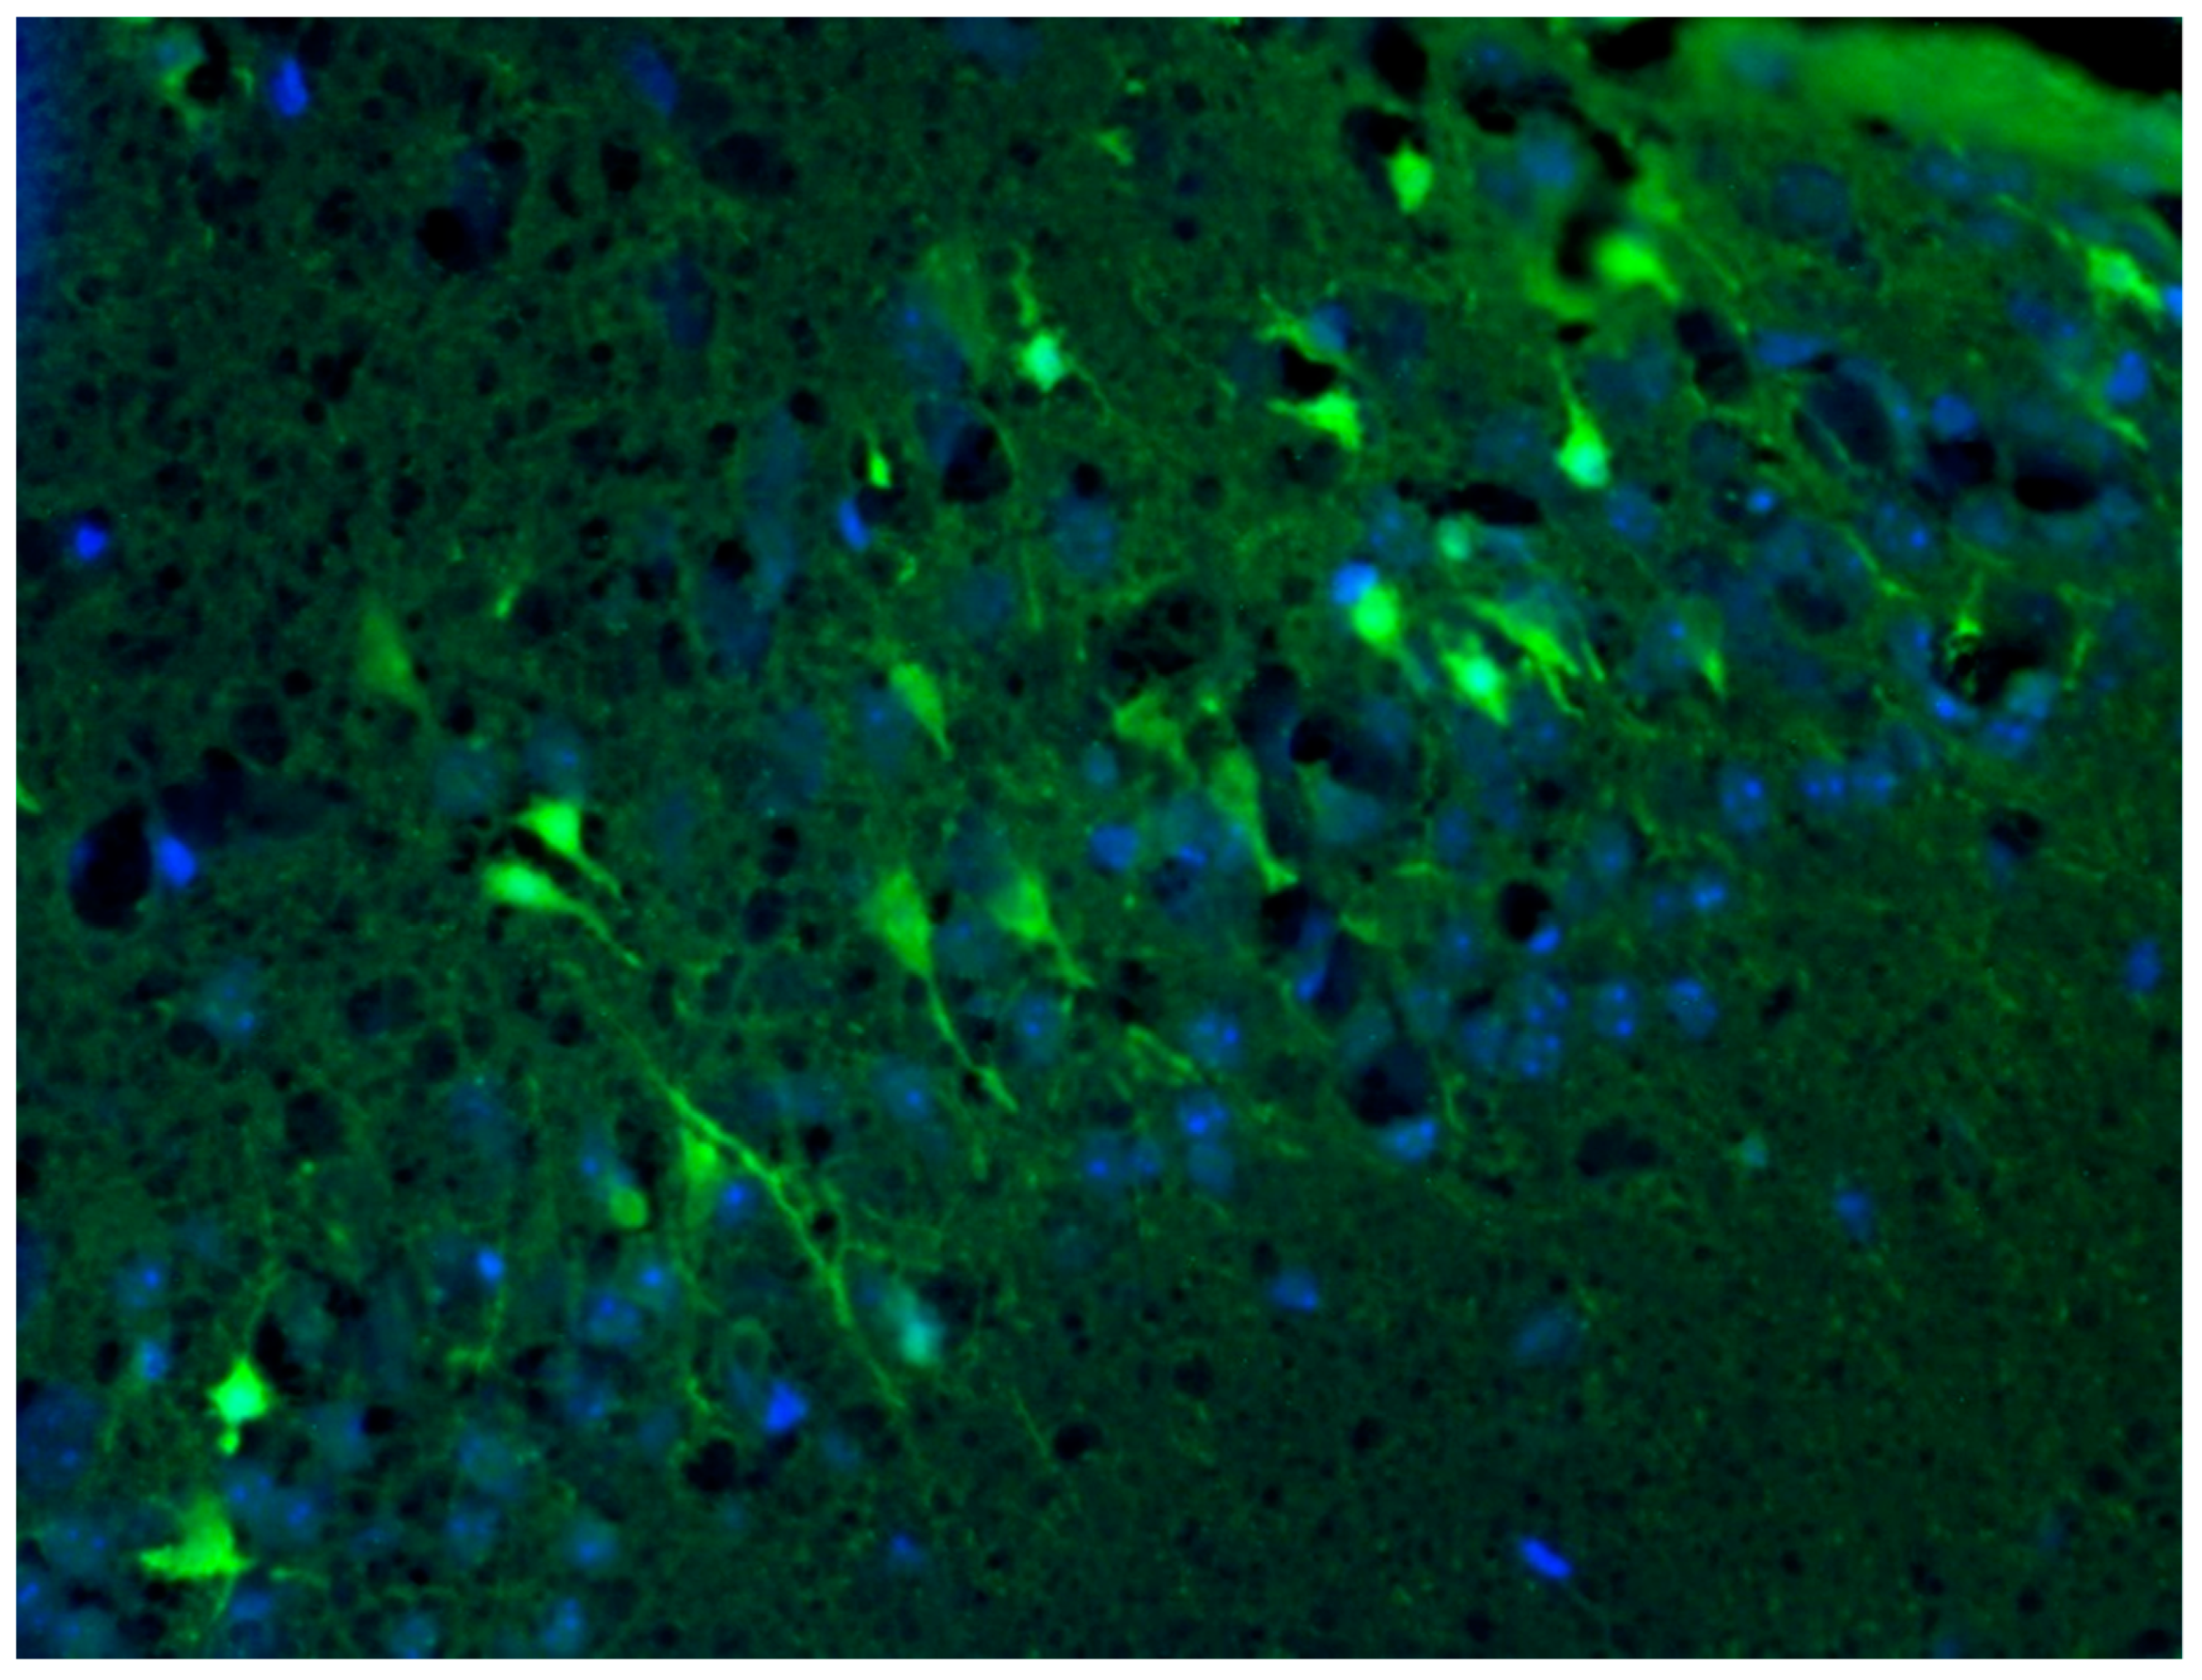

2.7. Detection of Neurodegeneration Localization Using Fluoro-Jade C Dye

3.7. Analysis of Intensity of Neurodegeneration in KA-Induced Experimental Epilepsy Model

3.8. Analysis of Localization of Neurodegeneration in KA-Induced Experimental Epilepsy Model